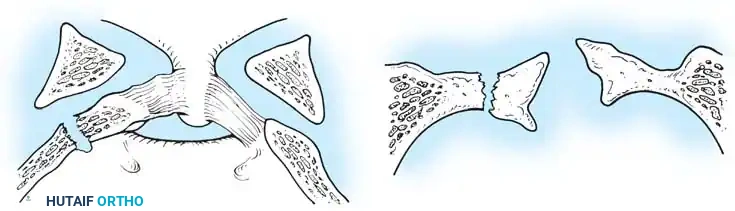

Fig 1. Important anterior and posterior supporting structures of the cervical spine. Understanding the integrity of the anterior longitudinal ligament, annulus fibrosus, and posterior ligamentous complex is paramount.

Fig 2. Diagrammatic representation of facet subluxation and dislocation mechanics.

* Stage 1: Failure of the PLC, evidenced by facet subluxation in flexion and abnormal divergence of the spinous processes (widened interspinous distance).

* Stage 2: Unilateral facet dislocation. Subluxation of the contralateral facet suggests severe ligamentous injury. Beatson's serial sectioning studies demonstrated that unilateral dislocation can occur with rupture of only the posterior interspinous ligament and the facet capsule.

* Stage 3: Bilateral facet dislocations, presenting with approximately 50% anterior subluxation of the vertebral body. This requires complete rupture of the interspinous ligament, both facet capsules, the posterior longitudinal ligament (PLL), and the annulus fibrosus.

* Stage 4: Full vertebral body width displacement anteriorly. This creates a grossly unstable motion segment, often termed a "floating" vertebra.